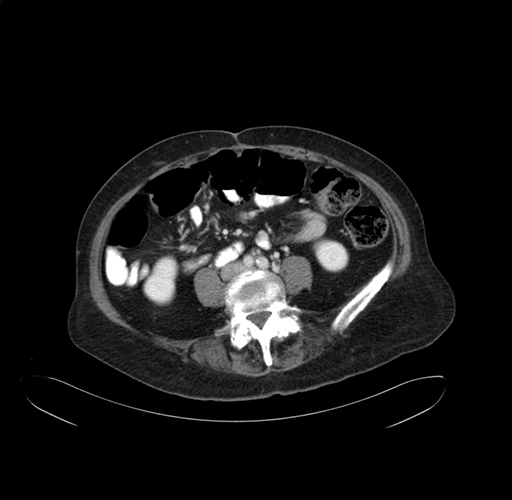

Pre-Chemo: Axial Venous